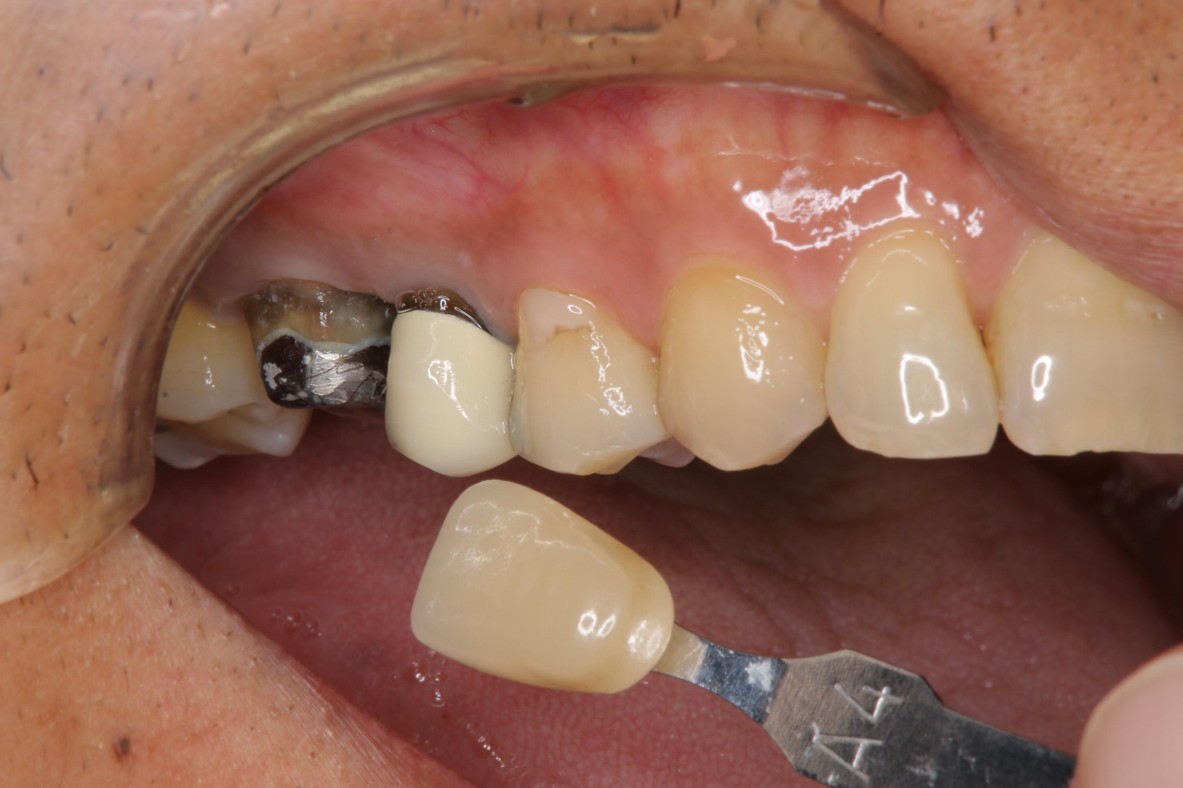

膺復前評估牙齦、牙齒狀態

照相比色